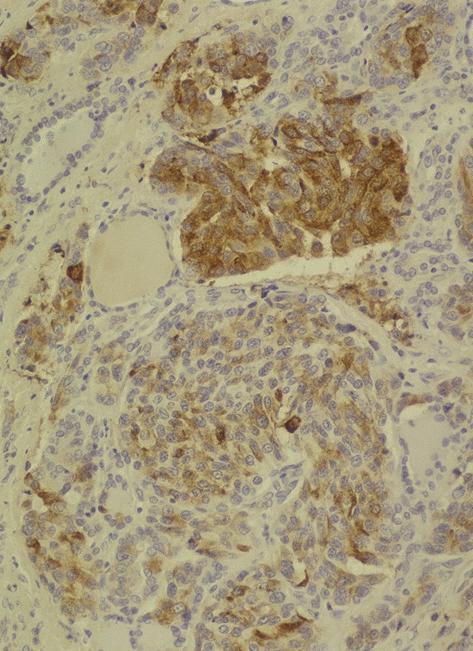

Microscopic (histologic) description

- Wide variety of morphology, can mimic any other thyroid malignancy

- Round, plasmacytoid, polygonal or spindle cells in nests, cords or follicles; often mixtures of these cells

- Round nuclei with finely stippled to coarsely clumped chromatin and indistinct nucleoli, occasional nuclear pseudoinclusion

- Eosinophilic to amphophilic granular cytoplasm due to secretory granules

- Generally low mitotic figures

- Stroma has amyloid deposits from calcitonin, prominent vascularity with glomeruloid configuration or long cords of vessels (Am J Surg Pathol 1995;19:642), coarse calcifications, occasional psammoma-like bodies

- Mucin in 42% (Arch Pathol Lab Med 1983;107:70)

- Often angiolymphatic invasion

- Occasionally marked neutrophilic infiltrate, oncocytic tumor cells, papillary patterns

- May entrap follicles

- C cell hyperplasia present in familial but not sporadic cases

Microscopic (histologic) images

Contributed by Shuanzeng Wei, M.D., Ph.D., Joseph Christopher Castillo, M.D. and Mark R. Wick, M.D.